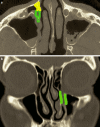

Endonasal endoscopic sinus surgery is the standard procedure for surgery of most paranasal sinus diseases. Appropriate frame conditions provided, the respective procedures are safe and successful. These prerequisites encompass appropriate technical equipment, anatomical oriented surgical technique, proper patient selection, and individually adapted extent of surgery. The range of endonasal sinus operations has dramatically increased during the last 20 years and reaches from partial uncinectomy to pansinus surgery with extended surgery of the frontal (Draf type III), maxillary (grade 3-4, medial maxillectomy, prelacrimal approach) and sphenoid sinus. In addition there are operations outside and beyond the paranasal sinuses. The development of surgical technique is still constantly evolving. This article gives a comprehensive review on the most recent state of the art in endoscopic sinus surgery according to the literature with the following aspects: principles and fundamentals, surgical techniques, indications, outcome, postoperative care, nasal packing and stents, technical equipment.